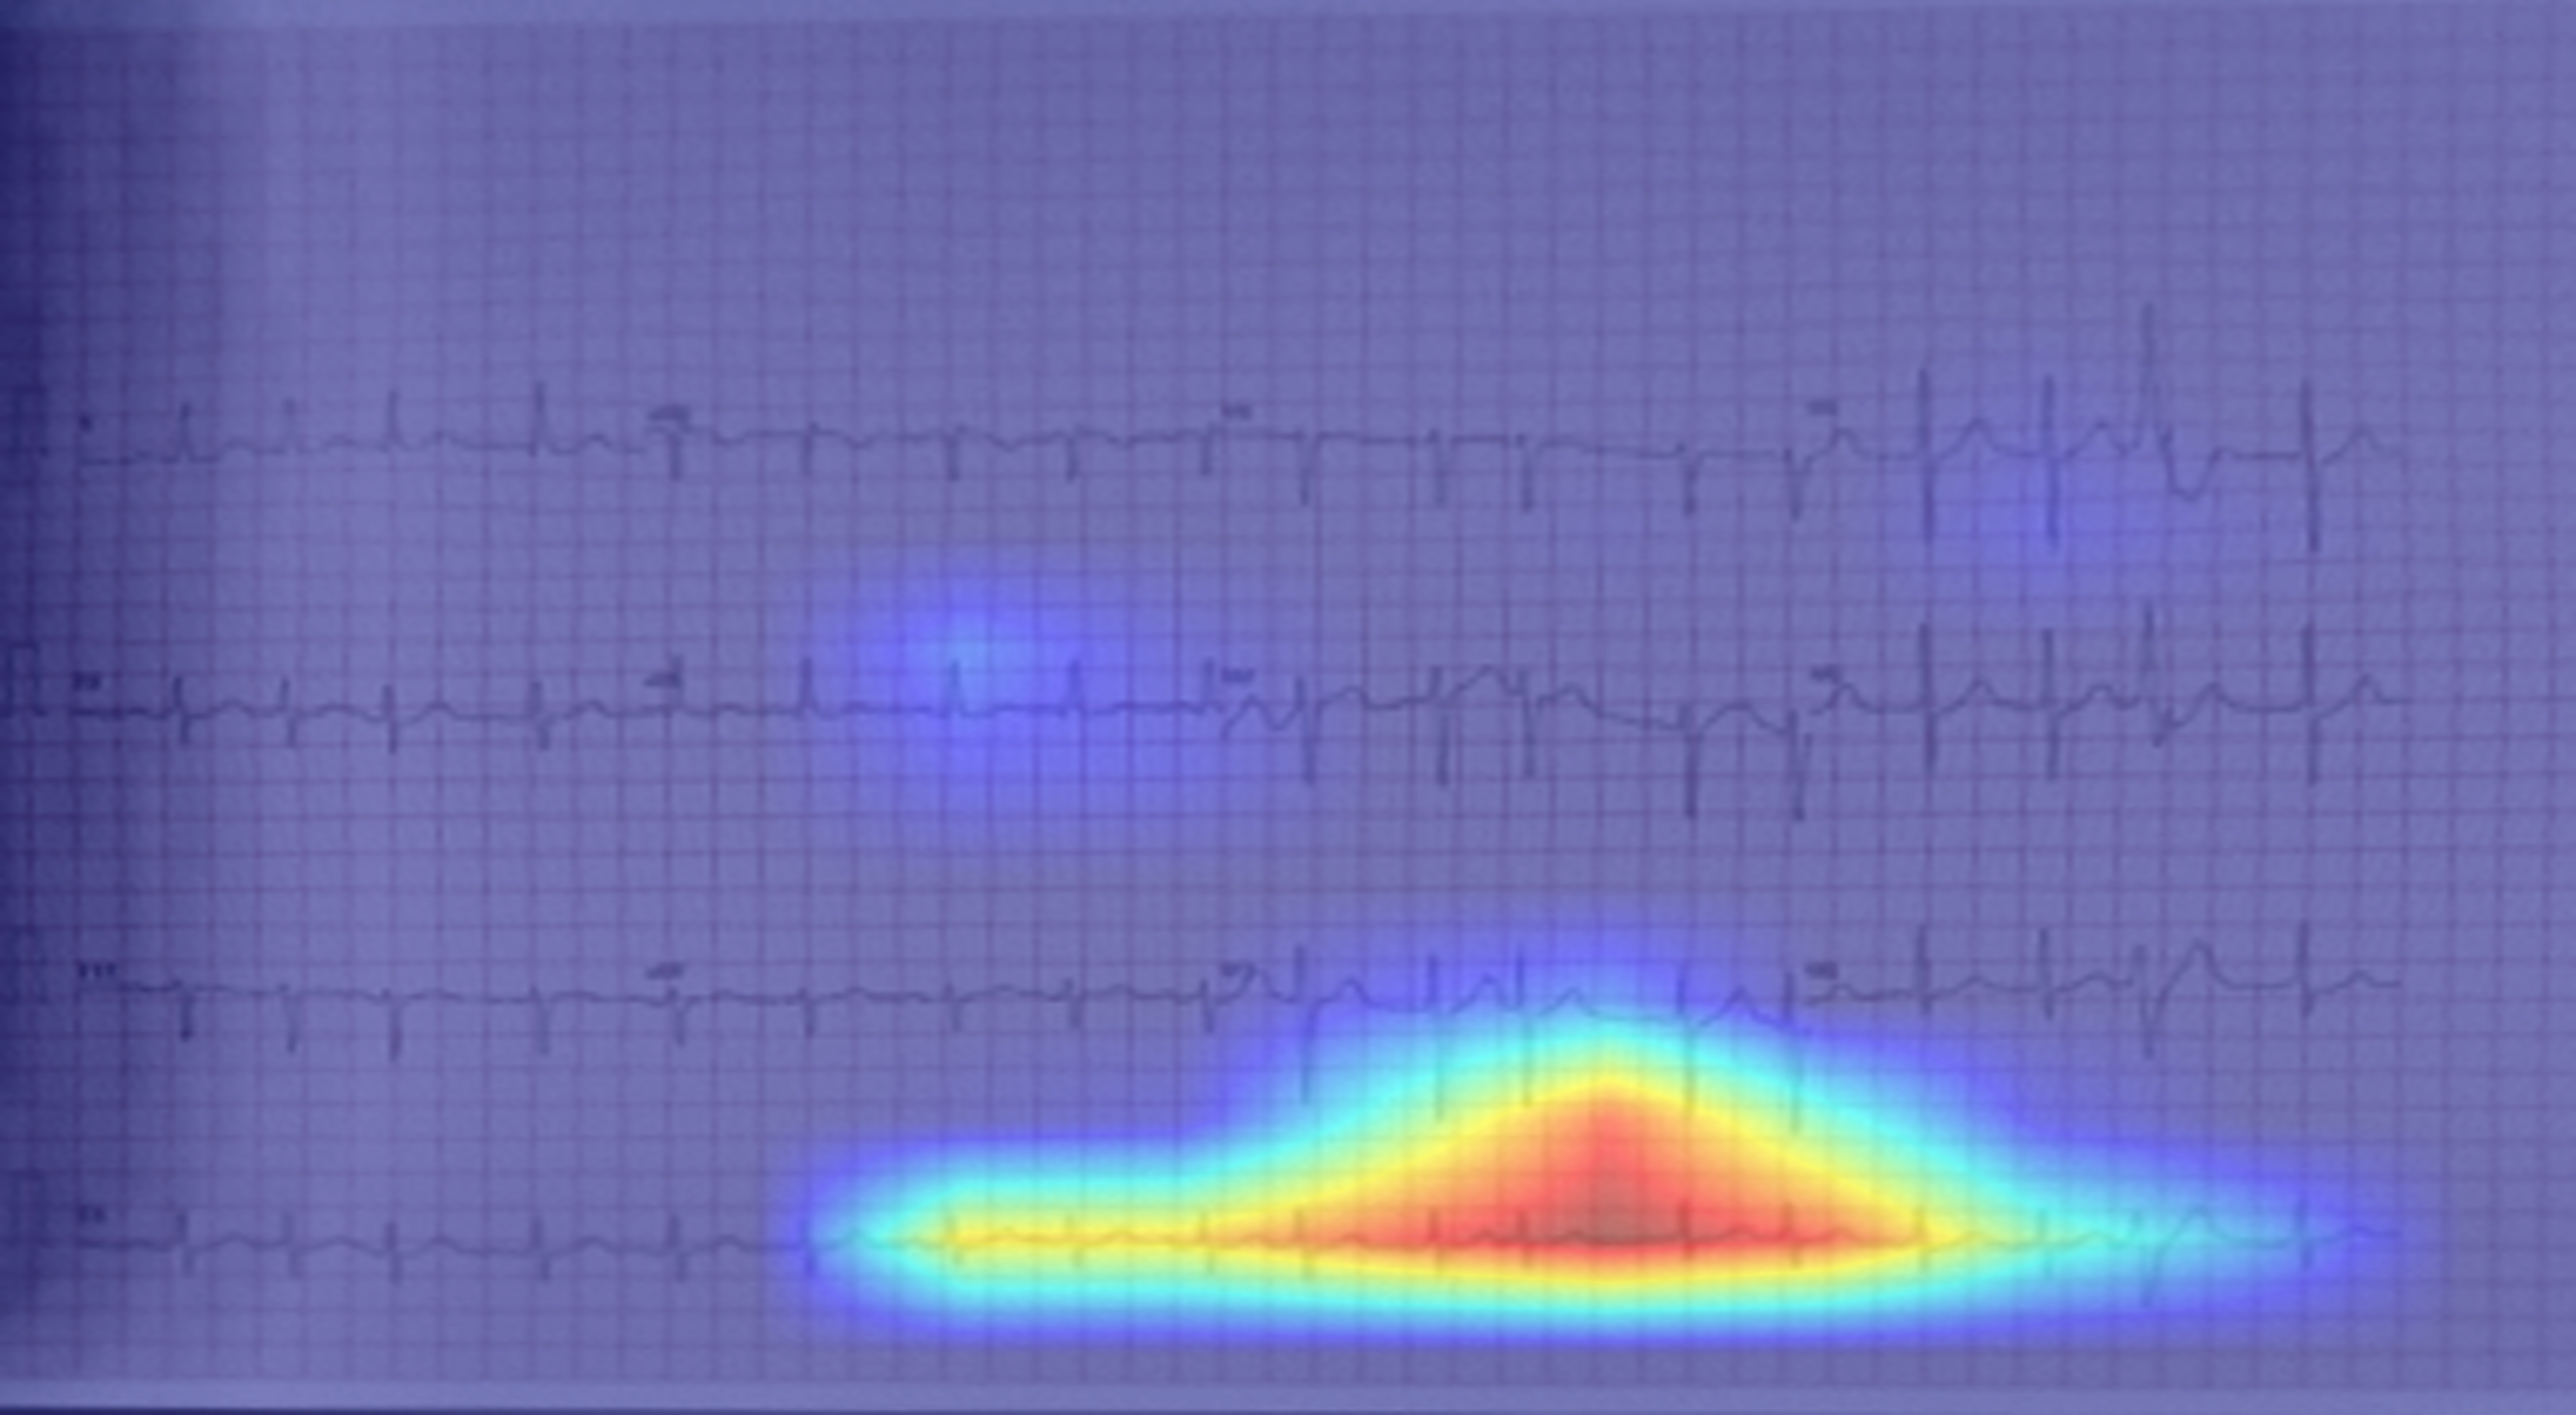

The Grad-CAM visualisations (Fig. 5) show that different pre-processing methods encourage the model to focus on different scales of information:

• 1.

ROI Crop + CLAHE preserves global context: Because this method retains the original layout and avoids aggressive transformations, the model processes the ECG as a continuous temporal signal. Figure 5b shows extended horizontal activation along the rhythm strip, indicating attention to temporal continuity. This is the appropriate strategy for detecting rhythm disorders such as Atrial Fibrillation (AF).

• 2.

Full Pipeline (Seg. + Rect.) emphasises local morphology: By segmenting and rectifying the image, this method enhances individual beats but reduces temporal information. As shown in Fig. 5c, the model concentrates on single-beat morphology. This benefits morphology-driven conditions such as Hypertrophy (Fig. 5f), but weakens rhythm analysis, resulting in lower performance on AF.

Refer to caption

(a) AF: Raw Input

(b) AF: ROI Crop + CLAHE

(c) AF: Full Pipeline (Seg. + Rect.)

(d) HYP: Raw Input

(e) HYP: ROI Crop + CLAHE

(f) HYP: Full Pipeline (Seg. + Rect.)

Figure 5: Grad-CAM visualizations for different pre-processing strategies on two samples: Atrial Fibrillation (AF, Top Row, a-c) and Hypertrophy (HYP, Bottom Row, d-f). (a, d) The Raw Input setting focuses on background noise. (b, e) The ROI Crop + CLAHE model shows a balanced focus that includes rhythm, which is the correct strategy for AF (b). (c, f) The Full Pipeline (Seg. + Rect.) model strongly prioritizes single-beat morphology. While this morphological focus is accurate for HYP (f), this bias toward morphology is less effective for the rhythm-based disorder AF (c).